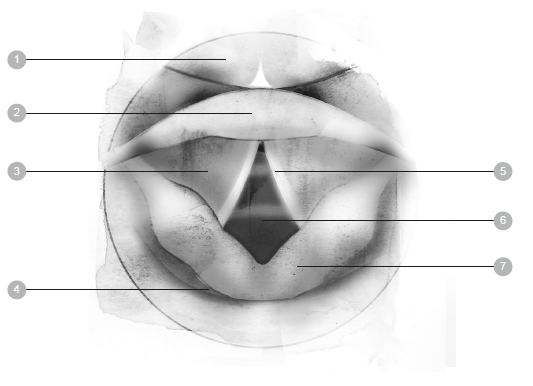

1 鼻子 6 肋间肌 11 气管

2 口 7 横膈膜 12 肺

3 会厌 8 鼻腔 13 支气管

4 胸膜 9 咽头(喉咙) 14 肺泡

5 肋骨 10 喉头